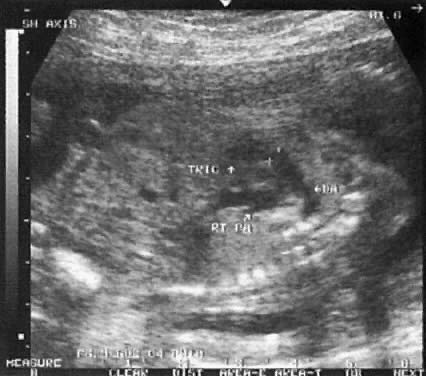

The short axis view (Fig. 7) encompasses the aortic and pulmonary valves as well as the ductus arteriosus and the right branch of the pulmonary artery. It is used to evaluate the size of the aorta and pulmonary arteries at the valvular level.

Fig. 7. Echogram of short axis view, depicting the tricuspid valve (TRIC) and the aortic valve to its right. The pulmonary valve is shown between the plus (+) signs. The pulmonary artery continues into the ductus arteriosus (DA). The right branch of the pulmonary artery (RT PA) is seen as it diverts to pass below the aorta.